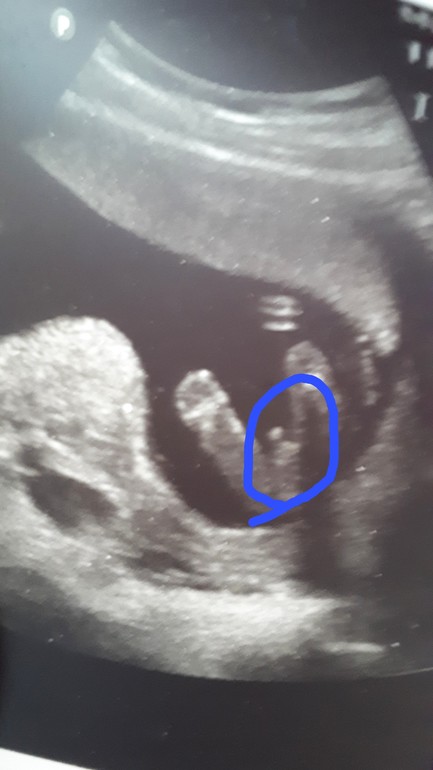

Пол малышаСходила на УЗИ, гематомка вроде рассосалась, предлежание пока еще низкое, но зев уже не перекрыт, ну и попытались разглядеть пол, предположили мальчика....сделали фото, говорят - "бубенчики видите?" А я вот по бубенчикам нифига не знаток😆

Мамы пацанчиков, посмотрите своим опытным взглядом - похоже на бубенчики?)))

Все на месте! И писюн и штуки) поздравляю!

Очень даже хорошие бубенчики 😇 поздравляю вас с мальчишкой, пусть родится в срок и здоровеньким 🤗😇🙏